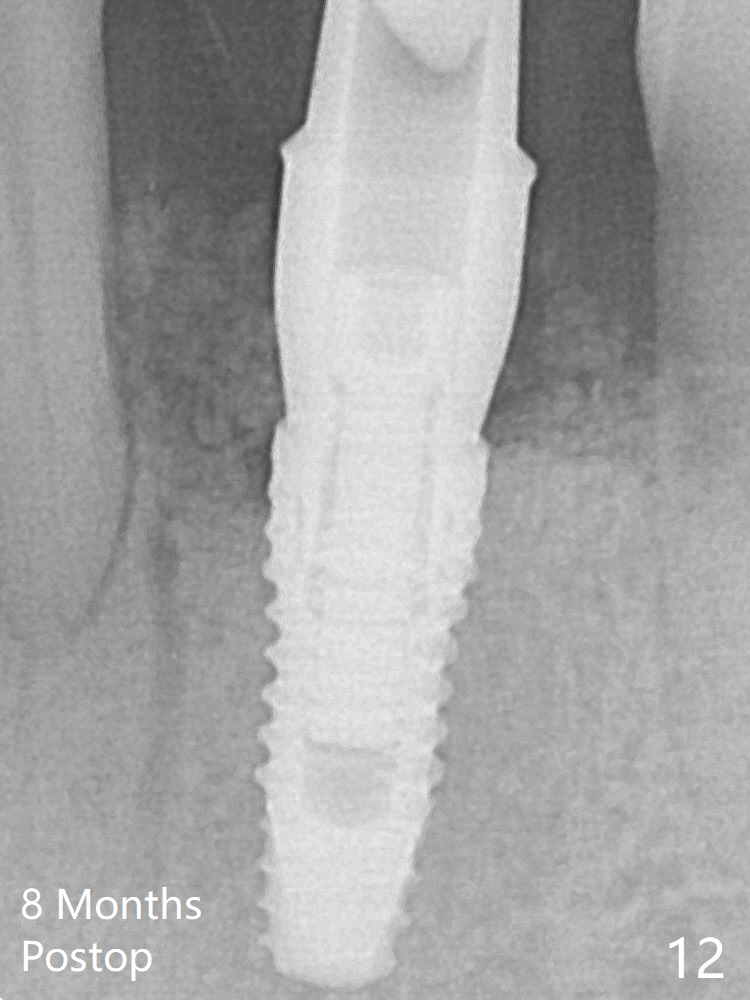

A 3.8x10 mm dummy implant is placed tentatively with an apical space (Fig.4 (the distal root surface of the lateral incisor is denuded (<)). When a same dimension definitive implant is placed with 40 Ncm, it is 2 mm below the lingual gingival margin, whereas 6-7 mm below the buccal one (Fig.5). Vanilla graft is placed before placement of a 5.5x4(5) mm abutment (Fig.6). The root surface of the lateral incisor is covered by the bone graft. Later the abutment is changed to a longer and smaller one (Fig.8) with more of the allograft (*). The short implant is chosen because it has to be placed deep to prevent periimplantitis, especially lingually, in spite of the fact of the unfavorable crown/implant ratio (Fig.4). The diameter of the implant is small so that there is ample space to pack bone graft both buccally and lingually. The majority of the bone graft seems to be in place 8 months postop (Fig.12).